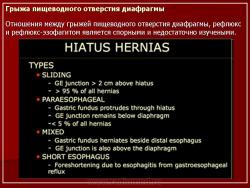

Согласно современным представлениям пищевод Барретта представляет собой замещение многослойного плоского неороговевающего эпителия пищевода цилиндрическим эпителием, нередко с явлениями кишечной метаплазии. Заболевание возникает в 10–20% случаев у больных гастроэзофагеальной рефлюксной болезнью (ГЭРБ) с частыми обострениями и продолжительным анамнезом (более 5 лет) рефлюкса. В пользу генетической предрасположенности формирования пищевода Барретта свидетельствует преобладание заболевания среди мужчин европеоидной расы. В литературе описано несколько случаев, в которых пищевод Барретта встречался чаще, чем в одном поколении у многих членов одной семьи. В этих семьях у одних членов была ГЭРБ без пищевода Барретта, а у других произошла трансформация в аденокарциному пищевода, что еще раз подчеркивает тесную связь между ГЭРБ, пищеводом Барретта и аденокарциномой пищевода, которые представляют собой последовательные стадии единого процесса. Однако в большинстве случаев пищевод Барретта носит не наследственный, а приобретенный характер. К предрасполагающим факторам пищевода Барретта относятся: грыжа пищеводного отверстия диафрагмы (ГПОД); прием лекарственных средств, снижающих давление нижнего пищеводного сфинктера (нитраты, антагонисты кальция, антихолинергические препараты, теофиллин), а также препаратов, вызывающих повреждение плоского эпителия (циклофосфамиды, метотрексат, фторурацил); изменение резистентности слизистой оболочки пищевода; агрессивность желудочного содержимого и др. Характерные клинические признаки, с помощью которых можно было бы выделить пациентов с пищеводом Барретта из общей группы больных ГЭРБ, отсутствуют. Эндоскопия с четырехкрантным взятием образцов биопсии остается клиническим стандартом для ведения пациентов с пищеводом Барретта. Эндоскопическая диагностика данного заболевания может осложняться нерегулярным характером Z-линии или зубчатой линии, являющейся местом соединения пищевода и желудка, переходом сквамозного эпителия пищевода в цилиндрический эпителий желудка с короткими (1–2 см) включениями желудочной слизистой оболочки в дистальной части пищевода. Целесообразно брать биоптаты из четырех квадрантов, начиная с гастроэзофагеального соединения и проксимально каждые 1–2 см к проксимальному краю слизистой оболочки пищевода Барретта, которая имеет характерный красный цвет и "бархатный" вид, что и отличает ее от расположенного рядом тонкого, бледного, с глянцевой поверхностью плоского эпителия. Ошибка при взятии образцов биопсии – проблема, которая ограничивает пользу выявления дисплазии как биомаркера злокачественности. Дисплазия пищевода Барретта чаще плоская, незаметная и неоднородная как по размерам, так и по тяжести. У ряда пациентов выполняли эзофагэктомии, поскольку при эндоскопическом обследовании была выявлена выраженная дисплазия без видимой опухолевой массы; инвазивный рак резецированных пищеводов был обнаружен в 30–40% случаев. Имеются описания предоперационных образцов биопсии, показавших внутрислизистую карциному, но резецированный пищевод данных больных не имел признаков рака.

Патогенез синдрома Маллори-Вейса

Разрыв слизистой оболочки кардии развивается во время сильных рвотных дижений. В основе резкое увеличение внутрижелудочного давления с растяжением стенок пищевода и желудка, неравномерное сокращение мышечного слоя стенок, сильный пассаж желудочного содержимого (особенно жидкости) из желудка в пищевод. Предрасполагающим моментом является грыжа пищеводного отверсия диафрагмы (что тоже может явиться результатом неоднократной сильной рвоты).